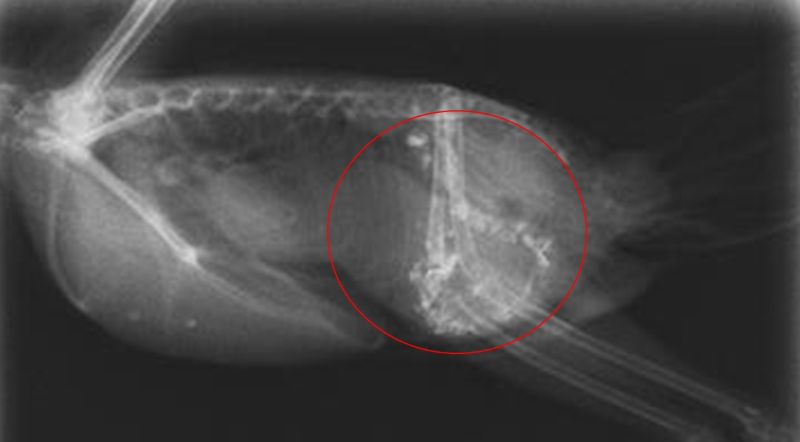

胃腸炎

未消化の粒がそのまま排せつされる全粒便や、胃出血による黒色便(メレナ)、粘液便、下痢などの症状がみられます。原因は様々で、細菌、真菌、寄生虫の感染、ボレー粉や砂の食べすぎによる胃腸の物理的損傷(図3)、換羽(羽が生え換わること)による疲労などがあります。予防としては、砂は与えない、ボレー粉の多給は避ける、換羽や季節の変わり目など体調不良を起こしやすい時期は温度管理と栄養管理を徹底するなどの対応が有効です。